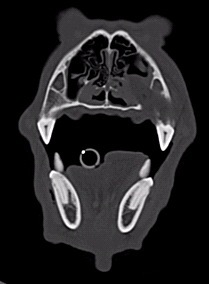

Für eine ausführliche Untersuchung der Maulhöhle sowie eine Computertomographie  (CT) wurde Timo anschließend kurz in Narkose gelegt. Im CT konnte man eine mottenfraßartige Auflösung des Kieferknochens im Bereich der etwa 2,5 cm großen Umfangsvermehrung sowie eine Verbindung zwischen der Schleimhaut der Maulhöhle und der rechten Nasenhöhle erkennen. Die regionären Lymphknoten waren etwas vergrößert. Der Brustkorb sowie das Lungengewebe stellten sich unauffällig dar. Das radiologische Bild der aggressiven Knochenläsion im rechten Oberkiefer mit begleitender Weichteilraumforderung war mit dem vermuteten Plattenepithelkarzinom in Einklang zu bringen.